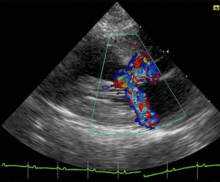

![]() |

Systolic anterior motion of the mitral valve

![]() Echocardiogram demonstrating systolic anterior motion of the anterior leaflet of the mitral valve |

Dynamic outflow obstruction (when present in HCM) is usually due to systolic anterior motion (SAM) of the anterior leaflet of the mitral valve. Systolic anterior motion of the mitral valve was initially thought to be due to the septal subaortic bulge, narrowing the outflow tract, causing high-velocity flow and a Venturi effect—a local underpressure in the outflow tract. Low pressure was thought to suck the mitral valve anteriorly into the septum. But SAM onset is observed to be a low-velocity phenomenon: SAM begins at velocities no different from those measured in normal hearts.[16][17] Hence, the magnitude and importance of Venturi forces in the outflow tract are much less than previously thought, and Venturi forces cannot be the main force that initiates SAM.

Recent echocardiographic evidence indicates that drag, the pushing force of flow, is the dominant hydrodynamic force on the mitral leaflets.[16][17][18][19][20][21] In obstructive HCM the mitral leaflets are often large[22] and are anteriorly positioned in the LV cavity[16][23] due to anteriorly positioned papillary muscles[16] that at surgery are often "agglutinated" onto the LV anterior wall by abnormal attachments.[20][21]

The mid-septal bulge aggravates the malposition of the valve and redirects outflow so that it comes from a lateral and posterior direction.[18] The abnormally directed outflow may be visualized behind and lateral to the enlarged mitral valve, where it catches it, and pushes it into the septum.[16][17][18][19] There is a crucial overlap between the inflow and outflow portions of the left ventricle.[24] As SAM progresses in early systole the angle between outflow and the protruding mitral leaflet increases. A greater surface area of the leaflets is now exposed to drag which amplifies the force on the leaflets – drag increases with increasing angle relative to flow.[18] An analogy is an open door in a drafty corridor: the door starts by moving slowly and then accelerates as it presents a greater surface area to the wind and finally it slams shut. The necessary conditions that predispose to SAM are: anterior position of the mitral valve in the LV, altered LV geometry that allows flow to strike the mitral valve from behind, and chordal slack.[16][17][18][19] SAM may be considered anteriorly directed mitral prolapse.[17][18][19] In both conditions the mitral valve is enlarged and is displaced in systole by the pushing force of flow resulting in mitral regurgitation.